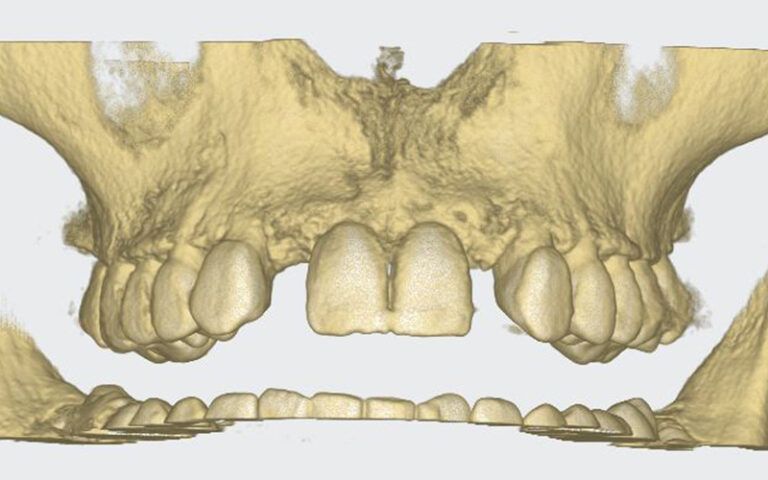

Patient’s initial CT scan after orthodontic treatment Patient’s initial CT scan after orthodontic treatment Patient’s initial CT scan after orthodontic treatment

STL images for planning STL images for planning STL images for planning

After this time a CBCT was taken of the maxilla to start planning the surgery for the placement of two implants in positions 12 and 22. During the analysis of the x-ray images, as the measurements indicate, it was observed that the mesio-distal space between 11-13 and 21-23 was limited, which would impede the placement of two standard implants with a diameter of 3.3 mm.